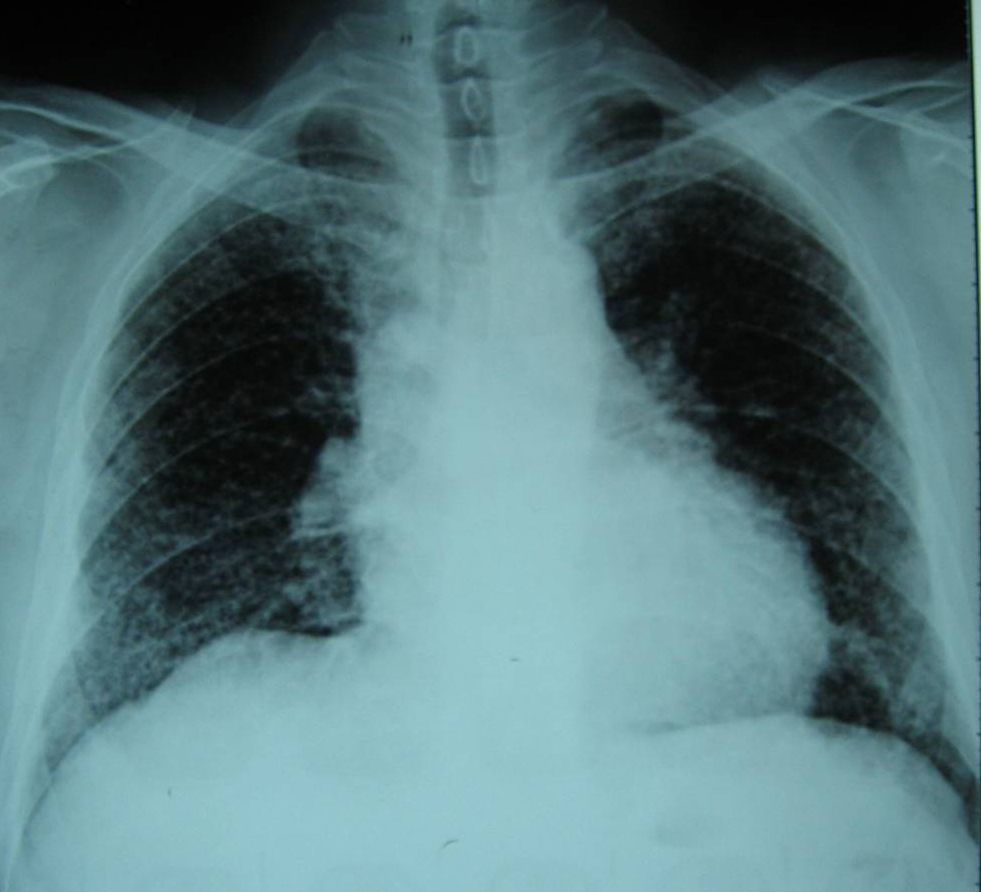

每日读片:肺朗格汉斯细胞组织细胞增生症

肺朗格汉斯细胞组织细胞增生症,少见的囊性间质性肺疾病